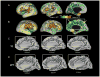

We analyzed long-lasting alterations in brain morphometry associated with preterm birth using volumetric and surface-based analyses applied to children at age 7 years. Comparison of 24 children born very preterm (VPT) to 24 healthy term-born children revealed reductions in total cortical gray matter volume, white matter volume, cortical surface area and gyrification index. Regional cortical shape abnormalities in VPT children included the following: shallower anterior superior temporal sulci, smaller relative surface area in the inferior sensori-motor cortex and posterior superior temporal cortex, larger relative surface area and a cingulate sulcus that was shorter or more interrupted in medial frontoparietal cortex. These findings indicate a complex pattern of regional vulnerabilities in brain development that may contribute to the diverse and long-lasting neurobehavioral consequences that can occur after very premature birth.